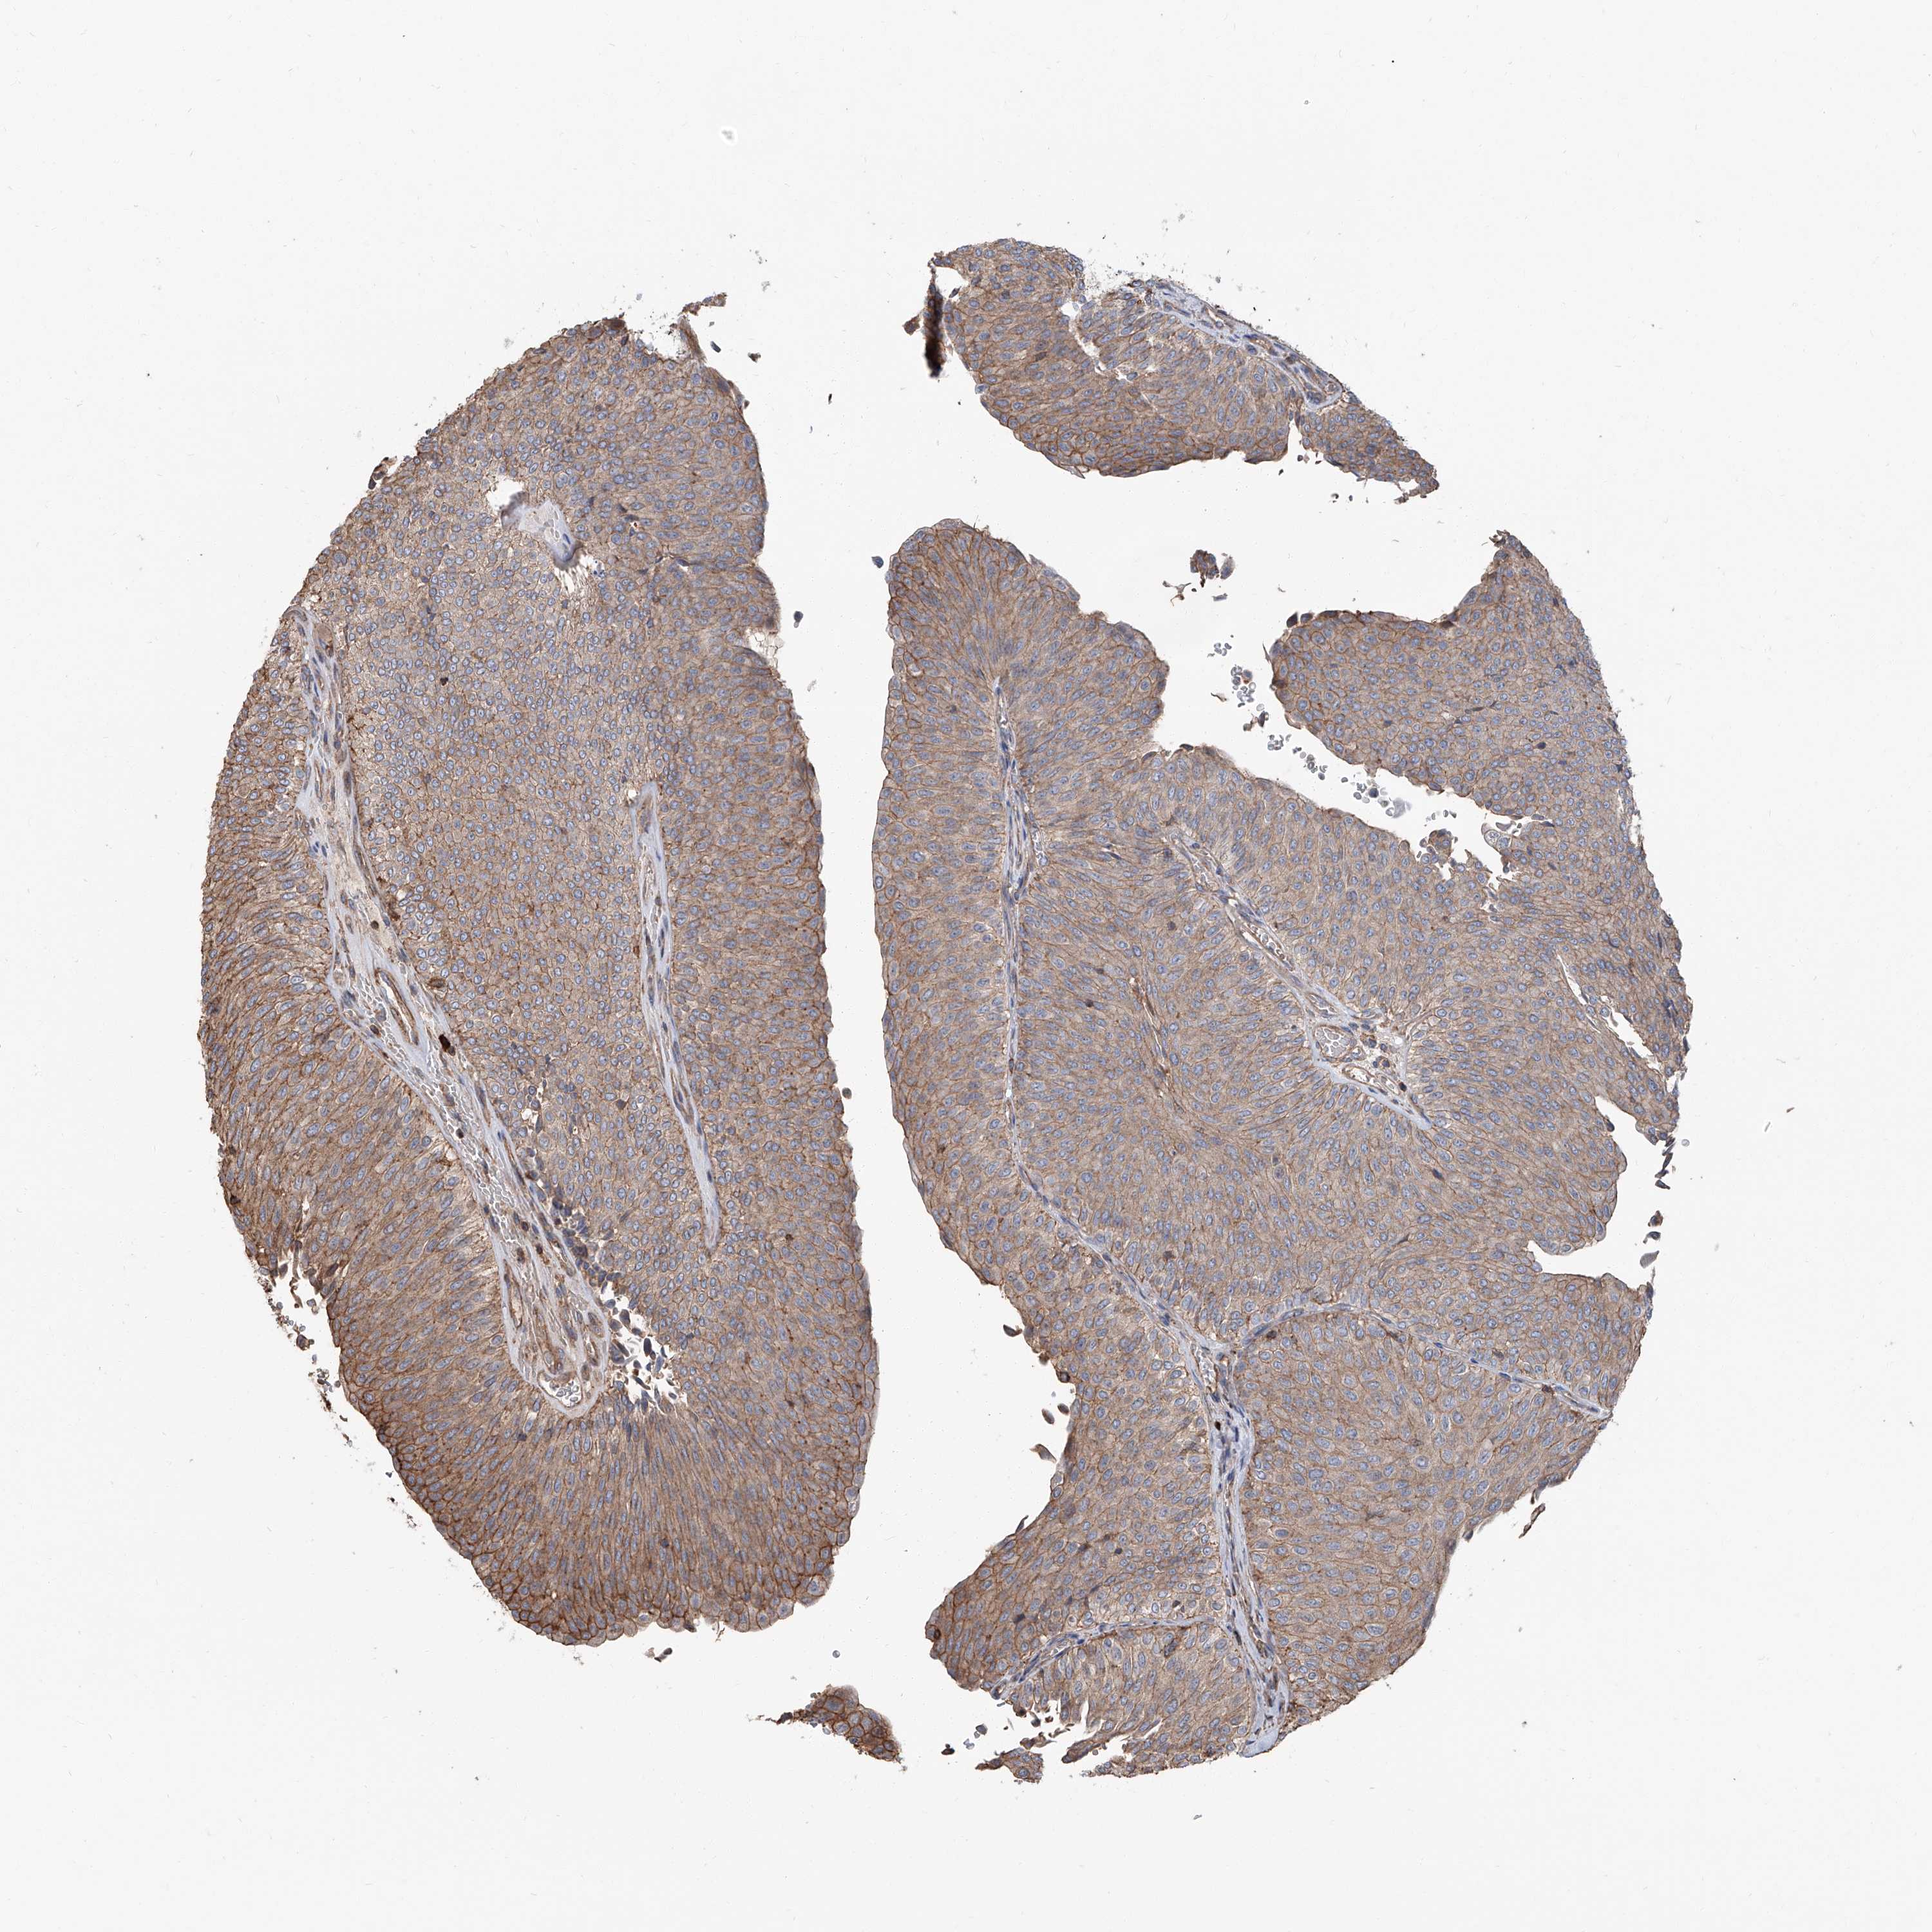

UROTHELIAL CANCER - Protein expressioni

A mouse-over function shows sample information and annotation data. Click on an image to view it in a full screen mode. Samples can be filtered based on level of antibody staining by selecting one or several of the following categories: high, medium, low and not detected. The assay and annotation is described here.

Note that samples used for immunohistochemistry by the Human Protein Atlas do not correspond to samples in the TCGA dataset.

Antibody stainingi

Antibody staining in the annotated cell types in the current human tissue is reported as not detected, low, medium, or high, based on conventional immunohistochemistry profiling in selected tissues. This score is based on the combination of the staining intensity and fraction of stained cells.

Each image is clickable and will lead to virtual microscopy that enables deeper exploration of all samples and also displays staining intensity scores, fraction scores and subcellular localization as well as patient and tissue information for each sample.

Antibody HPA015986

Antibody HPA031974

Antibody HPA040616

Urothelial carcinoma, Low grade

Urothelial carcinoma, High grade